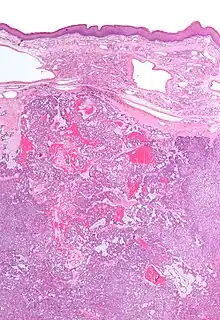

| Low magnification micrograph of a polymorphous low-grade adenocarcinoma, showing the typical variation of architectural arrangement. H&E stain. | |

Polymorphous low-grade adenocarcinoma (PLGA) is a rare, asymptomatic, slow-growing malignant salivary gland tumor.[1] It is most commonly found in the palate.[2]

- It has a varied microscopic architectural appearance, i.e. it is polymorphous.

PLGAs consist of a monomorphous cell population that has a varied histologic morphology.

Microscopically, its histology can be confused with an adenoid cystic carcinoma and a pleomorphic adenoma.